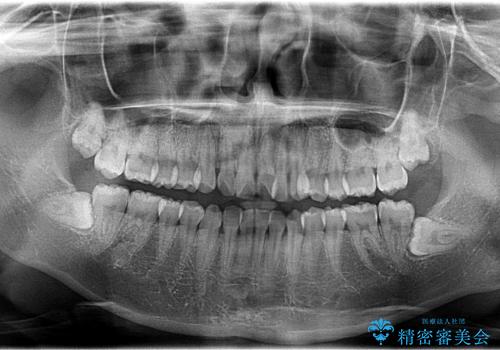

インビザラインによるガタつきの矯正治療 シンプル・短期間

- 20代女性

- invisalign full

- 1年6ヶ月

- 非抜歯、IPR+拡大によるマウスピース矯正を計画した。

一見前歯のガタつきだけのように見えても、そのガタつきの根本的な原因が奥歯の位置であったりすると、マウスピースの枚数がそれなりに多くなり、治療に時間がかかることもあります。